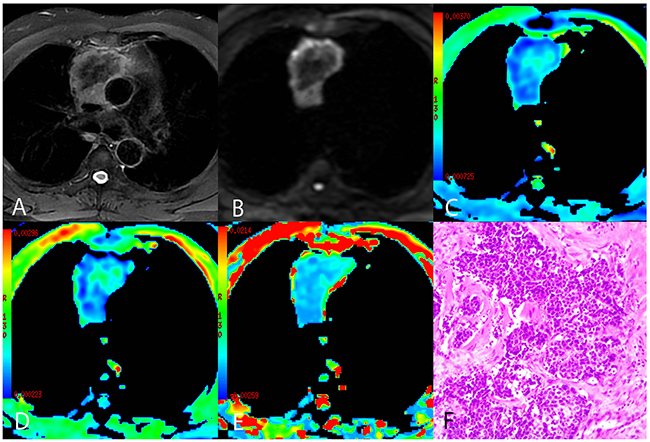

Figure 3: A representative case of thymic squamous cell carcinoma. (A) Axial T2-weighted fat-suppressed MR image showing an anterior mediastinal mass with an irregular contour containing a low-signal area. (B) Diffusion-weighted trace image (b = 1000 sec/mm2) showing peripheral high-signal intensity and central low-signal intensity. (C-E) ADCmb maps, D maps, and D* maps showing varying ADCmb, D, and D* values in different parts of the tumor (parametric values increase as color changes from dark blue to red). (F) Histological image showing carcinoma cells arranged in the nest with enlarged and atypical nuclei (HE, 200 ×). >ADCmb = ADC calculated using mono-exponential model DWI (multi b-values: 0 - 1200 sec/mm2); D = ADCslow or pure diffusion coefficient; D* = ADCfast or pseudo-diffusion coefficient.

Comparisons of the ADCmb and IVIM parameters among patients with LRT, HRT, and TC are shown in Table 3. A one-way ANOVA revealed that the mean ADCmb, D, and D* values in both readings were higher in the LRT group than in the HRT and TC groups (ADCmb: 1.55, 1.17, and 0.94 × 10−3 mm2/sec in the first reading (Figure 4A) and 1.56, 1.23, and 0.96 ×10−3 mm2/sec in the second reading; D: 1.09, 0.66, and 0.57 × 10−3 mm2/sec in the first reading (Figure 4B) and 1.14, 0.69, and 0.57 × 10−3 mm2/sec in the second reading; D*: 10.06, 4.93, and 3.35 × 10−3 mm2/sec in the first reading (Figure 4C) and 10.47, 5.29, and 3.90 × 10−3 mm2 /sec in the second reading, respectively; all P < 0.001); ADCmb and D values did not differ between the HRT and TC groups in either reading (first reading, P = 0.018 and 0.128 and second reading, P = 0.021 and 0.042 for ADCmb and D, respectively). In addition, the f value did not differ among any of the groups in either reading (P > 0.05) (Figure 4D). Representative ADCmb, D, and D* maps for patients with LRT (type A), HRT (type B3), and TC (thymic squamous cell carcinoma) are shown in Figure 1C-E, Figure 2C-E, and Figure 3C-E, respectively.

The mean values of all IVIM parameters were measured independently by two experienced radiologists, Y.-C.H. and G.-F. L, with 12 and 8 years of experience in thoracic MR imaging, respectively. First, they reviewed the conventional MR images carefully to locate the solid part of each tumor. Next, multi-b-value data were analyzed. A freehand region of interest (ROI) was traced using an electronic cursor and was placed to include the solid tumor elements based on the relative maximum signal intensity on the DW image (bright area, b=1000 sec/mm2, as shown in Figure 1B, Figure 2B and Figure 3B) and the relative minimum ADC value in the ADC map (deep-blue area, as shown in Figure 1C, Figure 2C, and Figure 3C), avoiding large vessels and hemorrhagic, calcified, cystic, and necrotic areas. The mean ROI area was 65.2 ± 24.6 mm2 (range, 26.0 - 120.0 mm2). The IVIM parameter maps were generated automatically (as shown in Figure 1C-E, Figure 2C-E, and Figure 3C-E) and the mean ADC, D, D*, and f values within the ROIs were obtained. The intra-class correlations (ICC) of the two measurements were analyzed to evaluate the consistency of the measurements taken by the two experimenters. The subsequent investigation of diagnostic efficacy was based on the first readings.